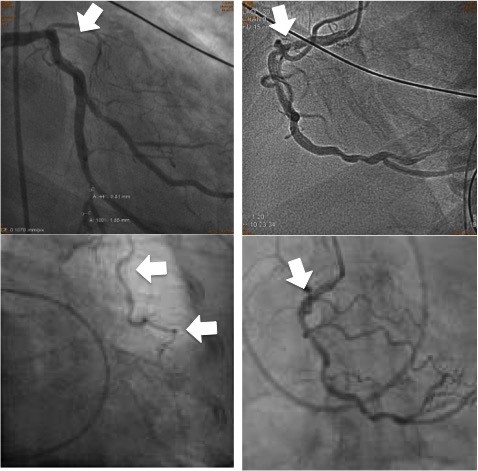

馬偕醫院心臟外科主任李君儀表示,該案老翁因冬泳讓原本就嚴重阻塞的冠狀動脈完全塞住,必須送往馬偕醫院進行治療,在心臟內、外科合作下,先在老翁左側胸腔打3個洞(2個1公分、1個5公分),再運用達文西機械手臂將老翁左內乳動脈銜接到完全阻塞的左前降支動脈,再由心臟內科接著在嚴重阻塞的右冠狀動脈放上支架,成功解決冠狀動脈阻塞救回老翁。